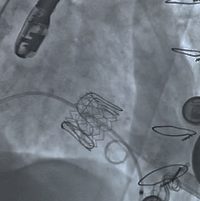

毁损生物瓣瓣架结构 瓣环内径测量

球扩瓣释放 术后左室造影无反流